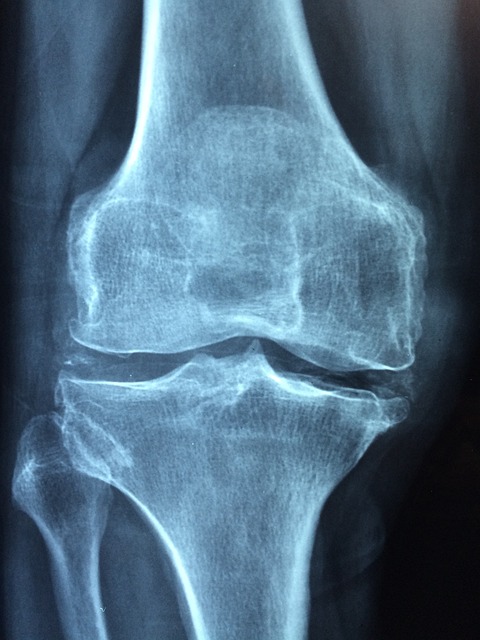

관절통의 원인으로 가장 많은 것이 관절의 노화라고 할 수 있는 변형성 관절증인데, 우리의 관절은 연골이 쿠션이 되어 부드럽게 움직일 수 있도록 만들어졌습니다. 그 연고가 나이가 들면서 부서지거나 빠지거나 줄어들거나 해서 주위에 염증을 일으키는 것입니다.

골관절염이 가장 일어나기 쉬운 곳이 무릎입니다. 무릎은 서 있는 것만으로도 전체 무게의 대부분을 지탱을 하기에 앉거나 일어날 때도 큰 힘이 가해집니다. 또한, 노화에 의해 다리의 근육이 약해지면 무릎에 대한 부담이 더욱 커지기에 무릎 통증을 일으키는 사람도 많이 있습니다.